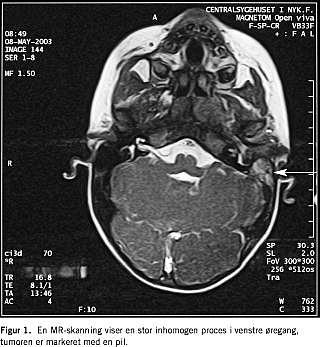

En MR-skanning (Figur 1 ) viste en stor inhomogen proces i meatus acusticus externus sin., ødem i tuba auditiva sin., m. pterygoideus medialis og lateralis sin. samt let ødem i mellemøret.